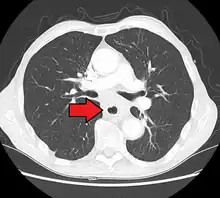

Although an occlusive tumor may be suspected on a barium swallow or barium meal, the diagnosis is best made with an examination using an endoscope. This involves the passing of a flexible tube with a light and camera down the esophagus and examining the wall, and is called an esophagogastroduodenoscopy. Biopsies taken of suspicious lesions are then examined histologically for signs of malignancy.

Additional testing is needed to assess how much the cancer has spread (see § Staging, below). Computed tomography (CT) of the chest, abdomen and pelvis can evaluate whether the cancer has spread to adjacent tissues or distant organs (especially liver and lymph nodes). The sensitivity of a CT scan is limited by its ability to detect masses (e.g. enlarged lymph nodes or involved organs) generally larger than 1 cm.[44][45] Positron emission tomography is also used to estimate the extent of the disease and is regarded as more precise than CT alone.[46] PET/MR as a novel modality has shown promising results in preoperative staging with fair feasibility and good correlation in comparison to PET/CT. It can enhance tissue differentiation with lowering the radiation dose to the patient.[47] Esophageal endoscopic ultrasound can provide staging information regarding the level of tumor invasion, and possible spread to regional lymph nodes.

Endoscopy and radial endoscopic ultrasound images of a submucosal tumor in the central portion of the esophagus- Contrast CT scan showing an esophageal tumor (axial view)